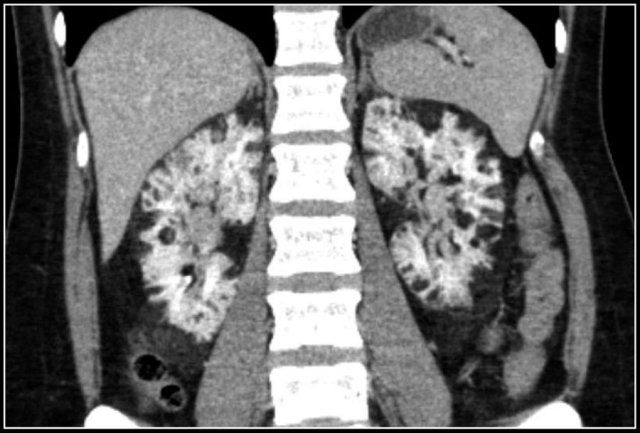

Multiple Angiomyolipomas

Sporadic AML is typically small, unilateral and asymptomatic, usually seen as an incidental finding.

In 10-20% of cases angiomyolipomas are multiple and bilateral.

This is mainly seen in patients with tuberous sclerosis.

Bleeding in Angiomyopiloma

Due to the abnormal vessels within an AML, it is prone to bleeding.

Patients can present with acute flank pain due to spontaneous hemorrhage.

The risk of hemorrhage increases with size.

Embolization was performed to stop the bleeding.

Preventive embolization is recommended in tumors larger than 4 cm, even in asymptomatic patients.

Notice the large vessels in the AML in the left kidney.